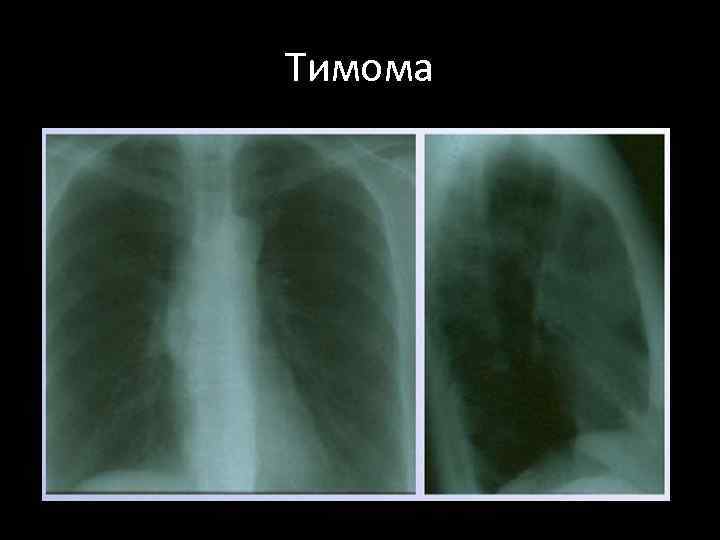

Тимома

Семиотика доброкачественных тимом • Локализуется асимметрично в среднем этаже переднего средостения • При глотании не смещается • Форма овоидная, неправильно шаровидная, грушевидная • Сплющена в передне-заднем размере, прижата к грудине • Поверхность бугристая, контуры четкие • Структура однородная, известковые включения встречаются крайне редко • Отграничена капсулой